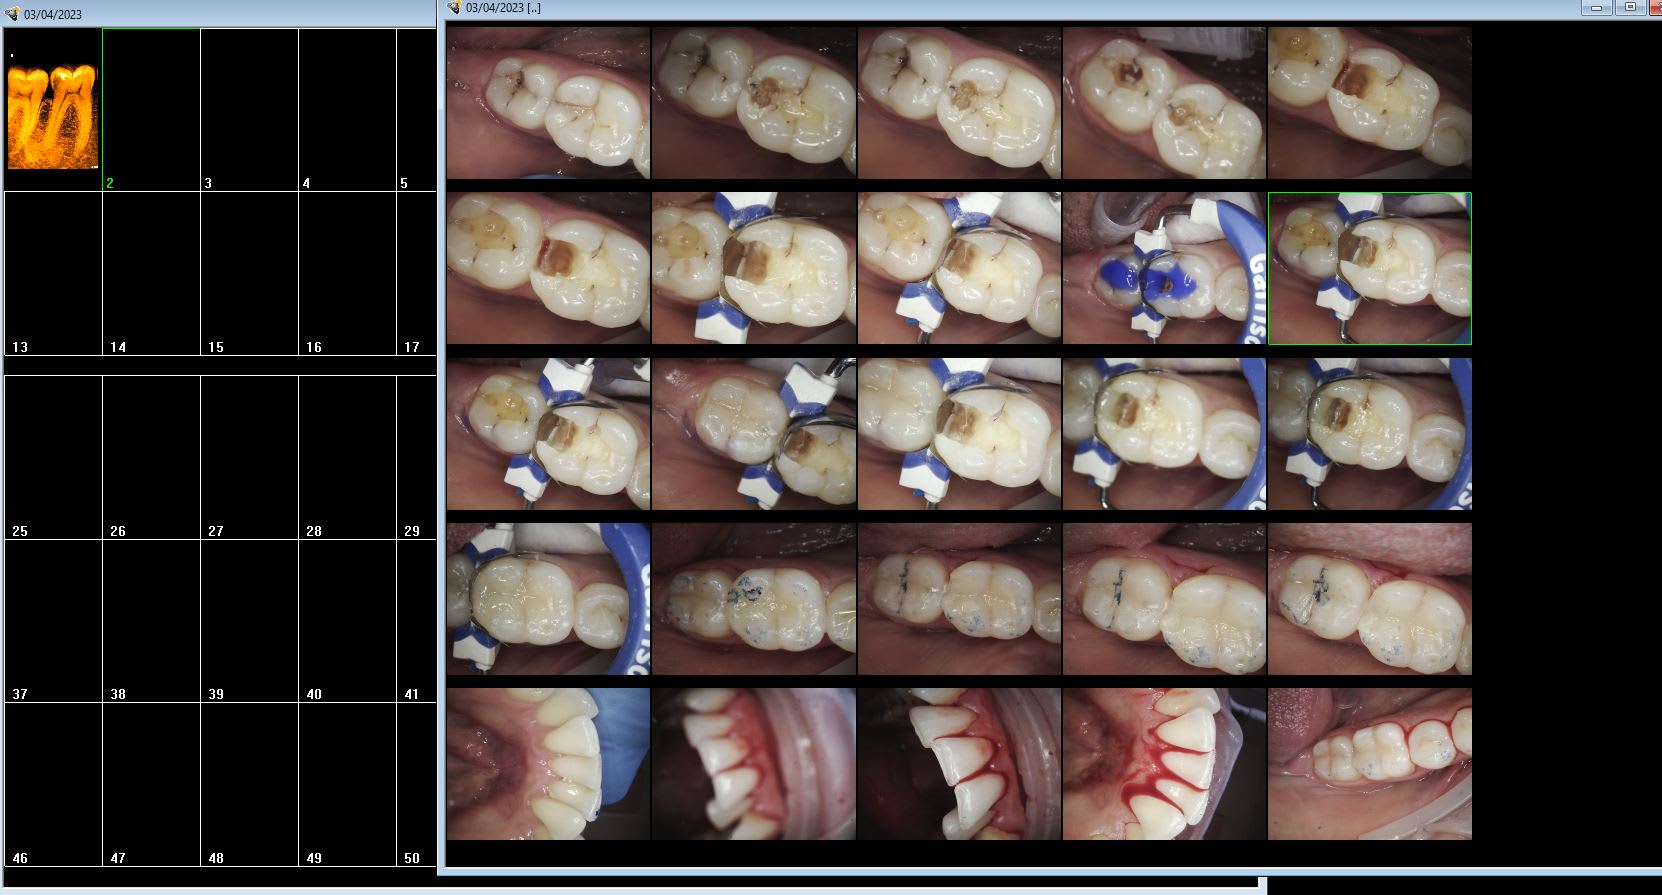

Cavités préparées sous anesthésie reconstituées par inlay compo extemporané chez l'adulte ou l'ado.